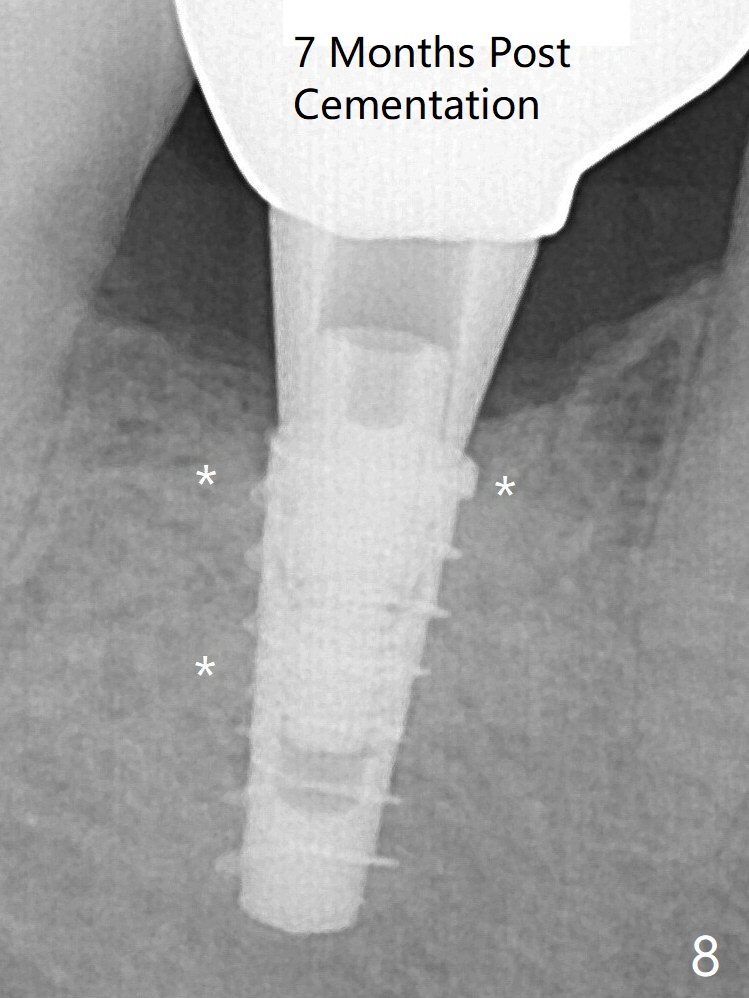

For safety, a 4x9 mm IBS implant is placed with insertion torque 40 Ncm; a 5x5.7(4) mm abutment is immediately placed for an immediate provisional to cover the large socket and keep Vera graft in place (Fig.4 *). Yellow dashed line: apical osteotomy; red dashed line: Mental Loop. Impression is taken nearly 3 months postop (Fig.6). The bone density around the implant increases 7 months post cementation (Fig.8 *). The higher density bone seems to extend coronally 1 year 7 months post cementation (Fig.9).